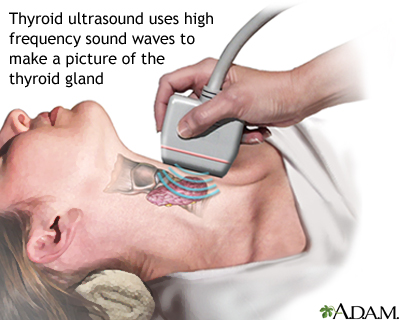

An ultrasound machine makes images so that organs inside the body can be examined. The machine sends out high-frequency sound waves, which reflect off body structures. A computer receives the waves and uses them to create a picture. Unlike with an x-ray or CT scan, this test does not use ionizing radiation.

- A clear, water-based gel is applied to the skin on the area to be examined. The gel helps with the transmission of the sound waves.

- A handheld probe called a transducer is moved over the area being examined. You may need to change position so that other areas can be examined.

- Thyroid